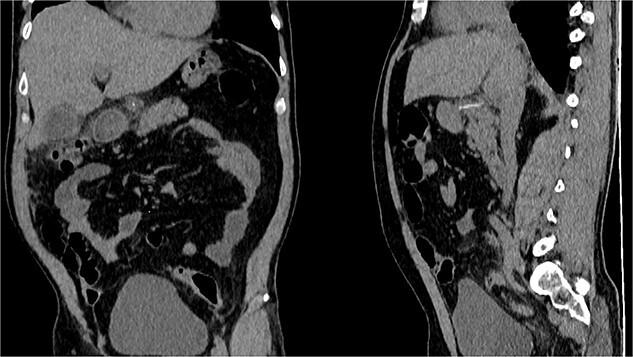

鱼骨穿孔致胃进入小网膜囊及胰腺并形成脓肿,这可不是件小事。

Fishbone perforation of the stomach into the lesser sac and pancreas with abscess, a fishy business.

Ingestion of foreign bodies is common in critical practice. Thankfully, most of these objects will pass without complications; however, sharp and metallic objects can cause severe complications like ulcers and perforation. Perforation of the gastrointestinal tract is rare; however, once it happens, prompt treatment is needed to prevent dreadful complications. We present the case of a 52-year-old patient who presented with abdominal pain and fever. A tomography detected a fishbone perforation of the stomach, which was in the lesser sac attached to the pancreas. After surgery, the patient successfully recovered.

摘要

在重症医疗实践中,异物摄入很常见。幸运的是,大多数此类物体可自行排出而无并发症;然而,尖锐和金属物体可导致严重并发症,如溃疡和穿孔。胃肠道穿孔很少见;然而,一旦发生,需要及时治疗以预防可怕的并发症。我们报告一例52岁患者,其表现为腹痛和发热。断层扫描检测到胃内有一根鱼刺穿孔,位于与胰腺相连的网膜囊内。手术后,患者成功康复。